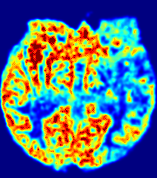

LesionRefer to captionRefer to captionRefer to captionRefer to captionRefer to captionRefer to caption𝐕rgbsubscript𝐕𝑟𝑔𝑏{\bf{V}}_{rgb}Refer to captionRefer to captionRefer to captionRefer to captionRefer to captionRefer to caption𝐕2subscriptnorm𝐕2{\|\bf{V}}\|_{2}Refer to captionRefer to captionRefer to captionRefer to captionRefer to captionRefer to captionRefer to caption3.53.53.52.82.82.82.12.12.11.41.41.40.70.70.70.00.00.0(mm/s)𝑚𝑚𝑠(mm/s)D𝐷DRefer to captionRefer to captionRefer to captionRefer to captionRefer to captionRefer to captionRefer to caption0.0200.0200.0200.0160.0160.0160.0120.0120.0120.0080.0080.0080.0040.0040.0040.0000.0000.000(mm2/s)𝑚superscript𝑚2𝑠(mm^{2}/s)Slice #1Slice #2Slice #3Slice #4Slice #5Slice #6

Figure 4: PIANO feature maps for another patient in the ISLES 2017 training set, where the lesion is located in the right hemisphere. Top row: segmented stroke lesion region (white) on different slices. The corresponding slices for the PIANO feature maps are shown in the following rows.

For a better insight into an estimated velocity field 𝐕𝐕{\bf{V}} and diffusion field 𝐃𝐃{\bf{D}}, we compute the following maps: (1) 𝐕rgbsubscript𝐕𝑟𝑔𝑏{\bf{V}}_{rgb}: Color-coded orientation map of 𝐕=(Vx,Vy,Vz)T𝐕superscriptsuperscript𝑉𝑥superscript𝑉𝑦superscript𝑉𝑧𝑇{\bf{V}}=(V^{x},V^{y},V^{z})^{T}, obtained by normalizing 𝐕𝐕{\bf{V}} to unit length and mapping its 3 components to red, green, blue respectively; (2) 𝐕2subscriptnorm𝐕2\|{\bf{V}}\|_{2}: 222 norm of 𝐕𝐕{\bf{V}}; (3) D𝐷D: scalar field in Eq. 5.

Fig. 3 and Fig. 4 show the PIANO feature maps estimated from two ISLES 2017 patients: all are highly consistent with the lesion in both cases. Details of the blood flow trajectories are revealed in 𝐕rgbsubscript𝐕𝑟𝑔𝑏{\bf{V}}_{rgb} by the ridged patterns and the sharp changes of colors in the unaffected (right) hemisphere, while the flat patterns appearing within the lesion provide little directional information about the velocity and indicate low velocity magnitudes. Velocity magnitudes are more directly visualized via 𝐕2subscriptnorm𝐕2\|{\bf{V}}\|_{2}, from which one can easily locate the lesion where 𝐕2subscriptnorm𝐕2\|{\bf{V}}\|_{2} is low. D𝐷D also indicates lower diffusion values in the lesion, though with less contrast potentially due to the fact that it captures the accumulated effect of CA diffusion at the voxel-level.